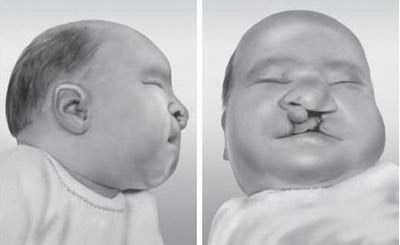

Внешние признаки синдрома Патау

- Аномальная форма черепа

При первом взгляде на младенца становится очевидным факт неправильного развития черепа. У больных он уменьшен, что в официальной медицине называется микроцефалией. Нарушение костей черепа, к сожалению, необратимо, потому что патология закладывается на ранних этапах формирования. Форма носа и ушных раковин искажена. Расстояние между глазами большое, переносица вогнутая. Уши больных посажены низко.

- Волчья пасть, заячья губа

Эти косметические дефекты – неизбежное следствие деформации костей черепа. Из-за расщелин процесс кормления заметно отягощается.

Новорожденные дети с синдромом ПатауУ детей с синдромом Патау отмечается ряд внешних отклонений и различных систем организма (см. фото новорожденных). Аномалии органов сильно взаимосвязаны между собой.

К внешним признакам синдрома Патау относятся:

Этот диагноз означает нарушение строения костей черепа (см. фото ниже).

Микроцефалия

МикроцефалияУ таких больных голова сильно меньше относительно здоровых детей. Данная патология не корректируется, так как череп ребенка формируется на ранних сроках беременности.

Расщелина нёба (заячья губа), возникает вследствие искаженной формы черепа. Данная патология может сделать процесс кормления малыша более трудоемким.

Синдром Патау: фото и отличительные признаки

Дети с подобной мутацией имеют ряд особых фенотипических характеристик. Для начала стоит сказать, что малыши рождают в срок, но с маленьким весом — имеет место пренатальная гипотрофия (вес доношенного ребенка с подобным диагнозом редко превышает 2500 г). Сам процесс родов также часто сопряжен с осложнениями, в частности асфиксией новорожденного.

Ребенок с хромосомной мутацией имеет ряд врожденных деформаций мозговой и лицевой части черепа. Имеет место микроцефалия — окружность головы малыша значительно меньше нормы. У детей с синдромом Патау лоб часто низкий и скощенный, переносица плоска и запавшая, а глазные щели узкие. Ушные раковины, как правило, деформированы и располагаются низко.

Типичным симптомом является и наличие двухсторонних расщелин лица, в частности, так называемой волчьей пасти (патология сопровождается расщеплением тканей мягкого и твердого неба, причем носовая и ротовая полости сообщены между собой), а также «заячьей губы» (расщелина губы). Врач может заподозрить наличие данной хромосомной мутации уже в первые часты после рождения ребенка.

Синдром Патау у детей: фото новорожденных

Такие дети внешне очень отличаются от нормальных. Невооруженным глазом видны расщелины, странный размер и строение черепа. Ушные раковины расположены очень низко.

- Особенности внешнего вида: килевидная деформация черепа, микроцефалия, атипичный размер и форма лба, близко посаженные орбиты, сужение глазной щели, широкий нос, низкие ушные раковины, вогнутая переносица, укороченный шейный отдел позвоночника. Больные рождаются с серьезными дефектами лица — расщелиной неба и верхней губы. Подобные уродства делают больного ребенка не похожим на человека.